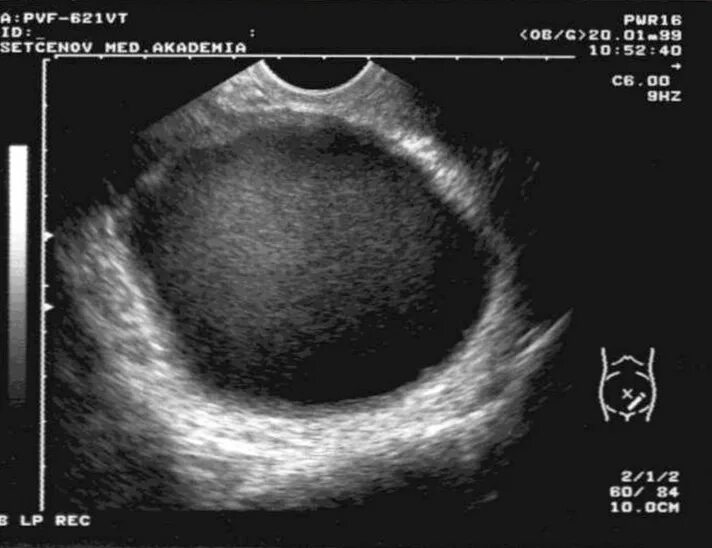

Киста уменьшается в размере